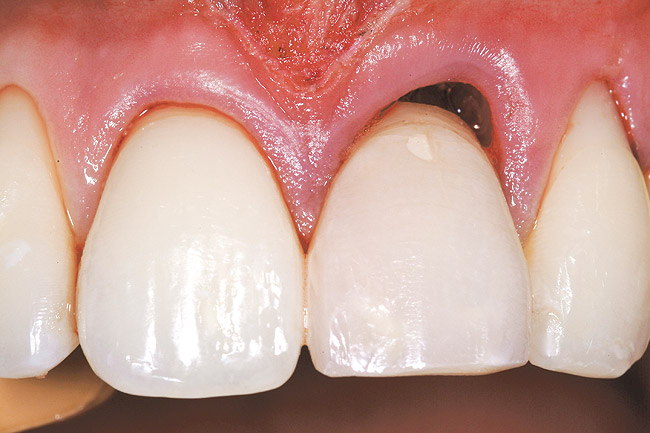

A 27-year-old non-smoking man presented for esthetic enhancement of the left central incisor, which had a pre-existing full-coverage restoration that required replacement (Figure 16). The patient had begun orthodontic treatment in the mandibular arch to correct a minor occlusal imbalance and required coronal repositioning and soft tissue grafting to correct gingival recession at the facial of the right canine, in addition to correction of the free gingival margin at the facial of the left central incisor, which was asymmetrical to the free gingival margin of tooth No. 8. Additionally, the facial gingival tissues were of a thin biotype, which at the facial surface of the left central incisor allowed for the darkened root surface to be visible through the tissue (Figure 16).

Figure 16  Case Two Preoperative clinical view, maxillary left central incisor.

Figure 16